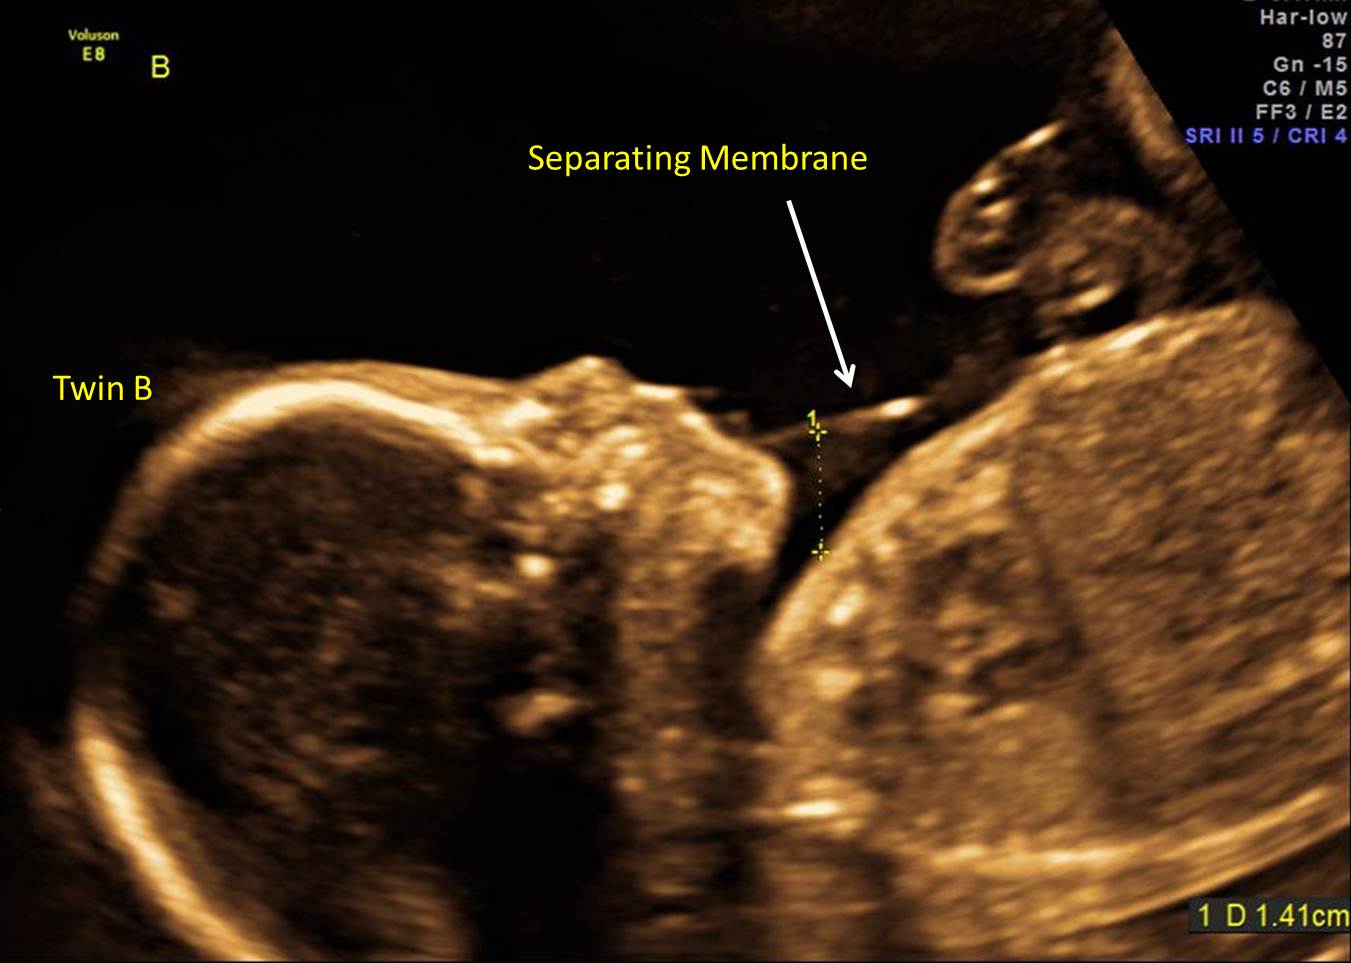

Twintwin transfusion syndrome. Comparative images between 2 affected What Is Twin To Twin Transfusion Because there is no barrier separating the two fetuses from each other, there are almost always. But an ultrasound as early as 10. Ttts affects identical twins (or higher multiple gestations) who share a common monochorionic placenta. twin to twin transfusion syndrome (ttts) is a disease of the placenta (or afterbirth) that affects identical twin pregnancies. what is. What Is Twin To Twin Transfusion.